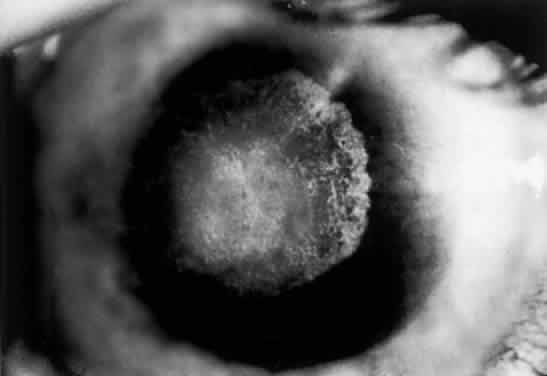

Nonsystemic Familial Type. Lattice corneal dystrophy (Biber-Haab-Dimmer) is usually considered to be a localized amyloidosis of the cornea and could be classified as a special type of primary localized autosomal dominant amyloidosis (see corneal dystrophies section) (Fig. 6).78 Rarely, a form of primary familial amyloidosis of the cornea may occur. The lesions appear as centrally located, raised, gelatinous masses with a mulberry-like surface (Fig. 7).79

CONJUNCTIVA. Clinically detectable conjunctival involvement is not a feature of systemic amyloidosis. However, nonfamilial amyloidosis confined to the conjunctiva has been reported as an example of primary amyloidosis. Conjunctival amyloidosis is often asymptomatic and may be present for years before the patient seeks medical attention. Typically, there is a discrete, nonulcerative, yellow, waxy, firm, nontender subconjunctival swelling (Fig. 8). This may be located in the palpebral fornix or bulbar conjunctiva, including the limbal area. The conjunctival area is usually smooth but may be friable and may show recurrent bleeding. However, antecedent local diseases have been incriminated in this amyloid deposition.77